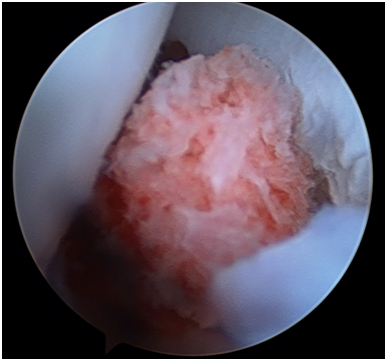

Figure 8 Bone Graft between the scaphoid pseudarthrosis.

Figure 9 Arthroscopic view of the graft.

The arthroscopic procedure started with the realization of standard radio-carpic initial portals; medium-carpal portals helped with the identification of the pseudarthrosis focus (Figure 4). The pseudarthrosis focus was blown out (Figures 5 & 6). The spongious graft of the contralateral iliac crest was harvested. Placement of the graft through the midcarpal portal of visualization by adapting the arthroscopy trocar (Figures 7-9). The traction was withdrawn. The graft was fixated with a percutaneous anterior approach and arthroscopic support and placement of the double compression screw with radiographic support (Figure 10).